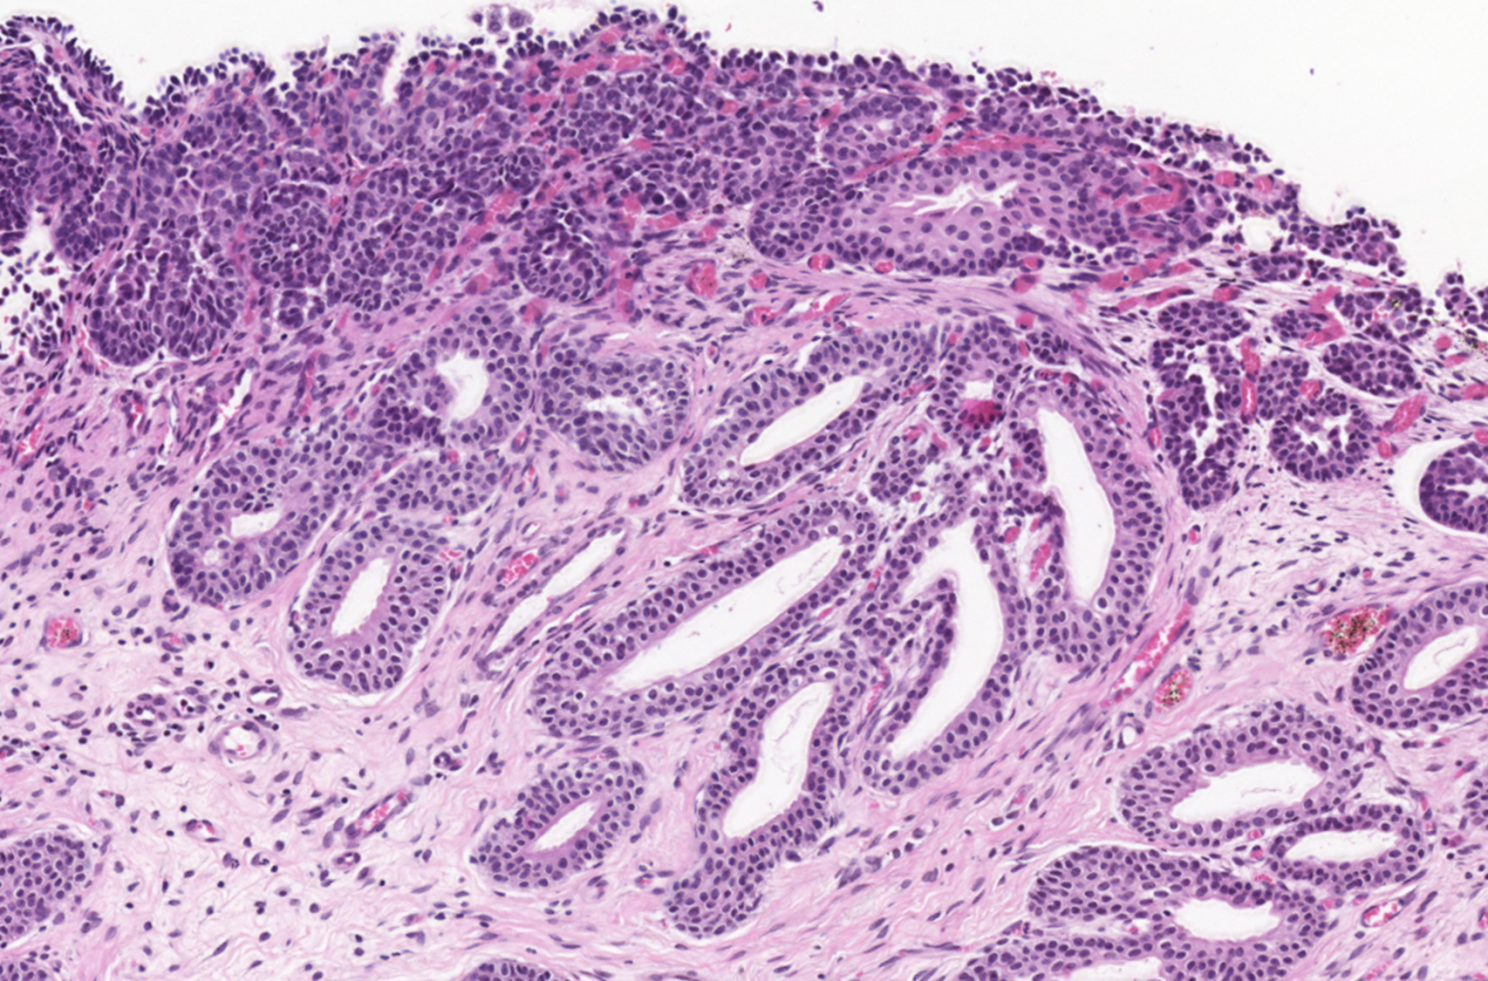

The polyps found in the bladder mucosa consist of a core of proliferative connective tissue covered by surface epithelium. This surface epithelium can form nests of hyperplastic urothelial cells in the lamina propria, known as Brunn’s nests, or undergo metaplasia to a mucus-secreting, glandular epithelial type, leading to a condition called CYSTITIS GLANDULARIS. These resulting polypoid masses may have a broad-based or pedunculated structure, occurring most frequently in the cranioventral bladder wall. Chronic haematuria, often unresponsive to antimicrobial therapy, is a common observation in cases of chronic polypoid cystitis. This bleeding is often associated with the breakdown of polyps, potentially promoting urine retention and bacterial introduction, thus establishing a cyclic pattern of infection, proliferation, and inflammation.

Histologically, our case had in lamina propria, occasionally extending from mucosa, multiple hyperplastic tortuous glands that were often cystic dilated. They were lined by one to multiple layers of uniform cuboidal or columnar epithelial cells, occasionally surrounded by a few layers of urothelial cells. They had no evident atypia. The lamina propria where they were immersed contained a few plasma cells, lymphocytes, neutrophils and rare histiocytes.